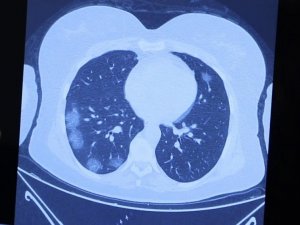

Koronanın nörolojik belirtileri

Korona virüsün nörolojik belirtileri

Profesörden korkutan korona açıklaması: "Virüs düşünen bir organizma gibi davranıyor"